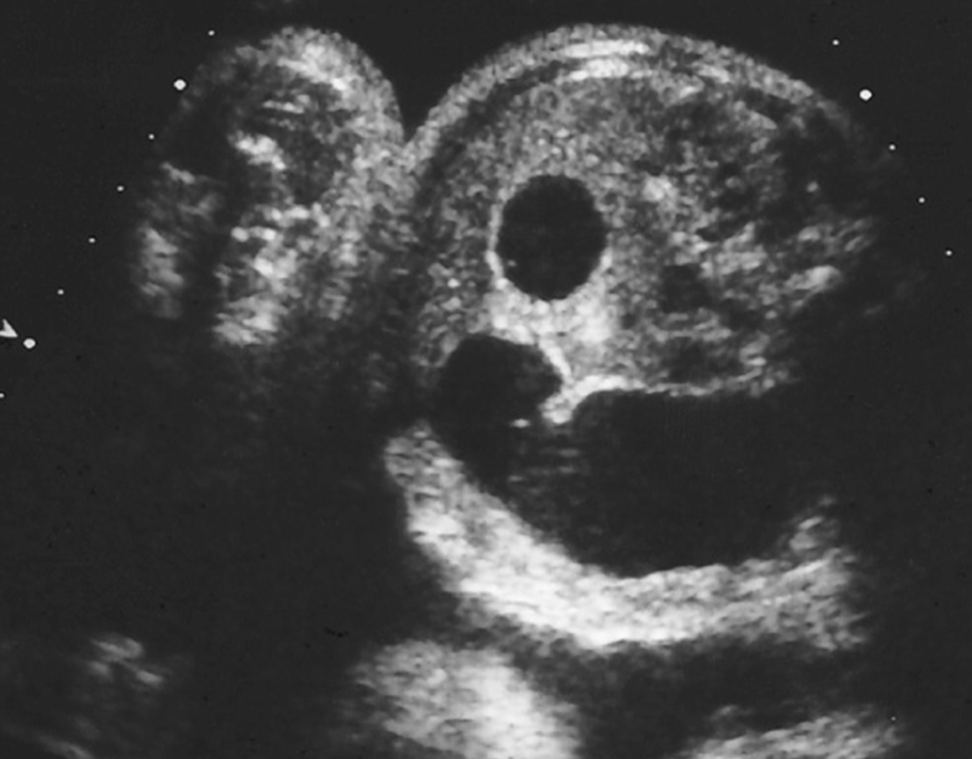

hydronephrosis